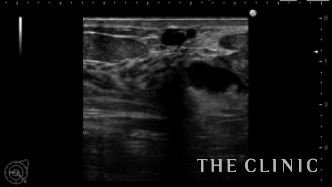

吸引した壊死脂肪です。(左)

オイルシストは穿刺吸引しました。(右)